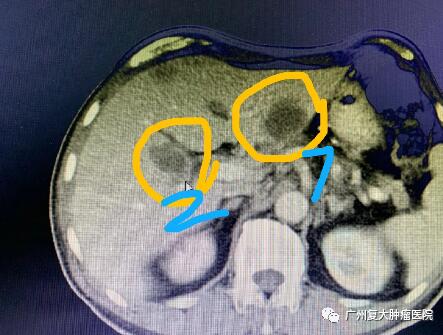

影像图片显示

图3

为减轻肿瘤负荷,改善生活质量,延长患者生命,经患者及家属同意,我院牛立志院长为其实行胰腺肿瘤、肝脏肿瘤不可逆电穿孔治疗,术中以胰腺肿瘤、肝脏10个病灶为靶区消融。术后联合化疗加免疫药物治疗进一步改善治疗效果。